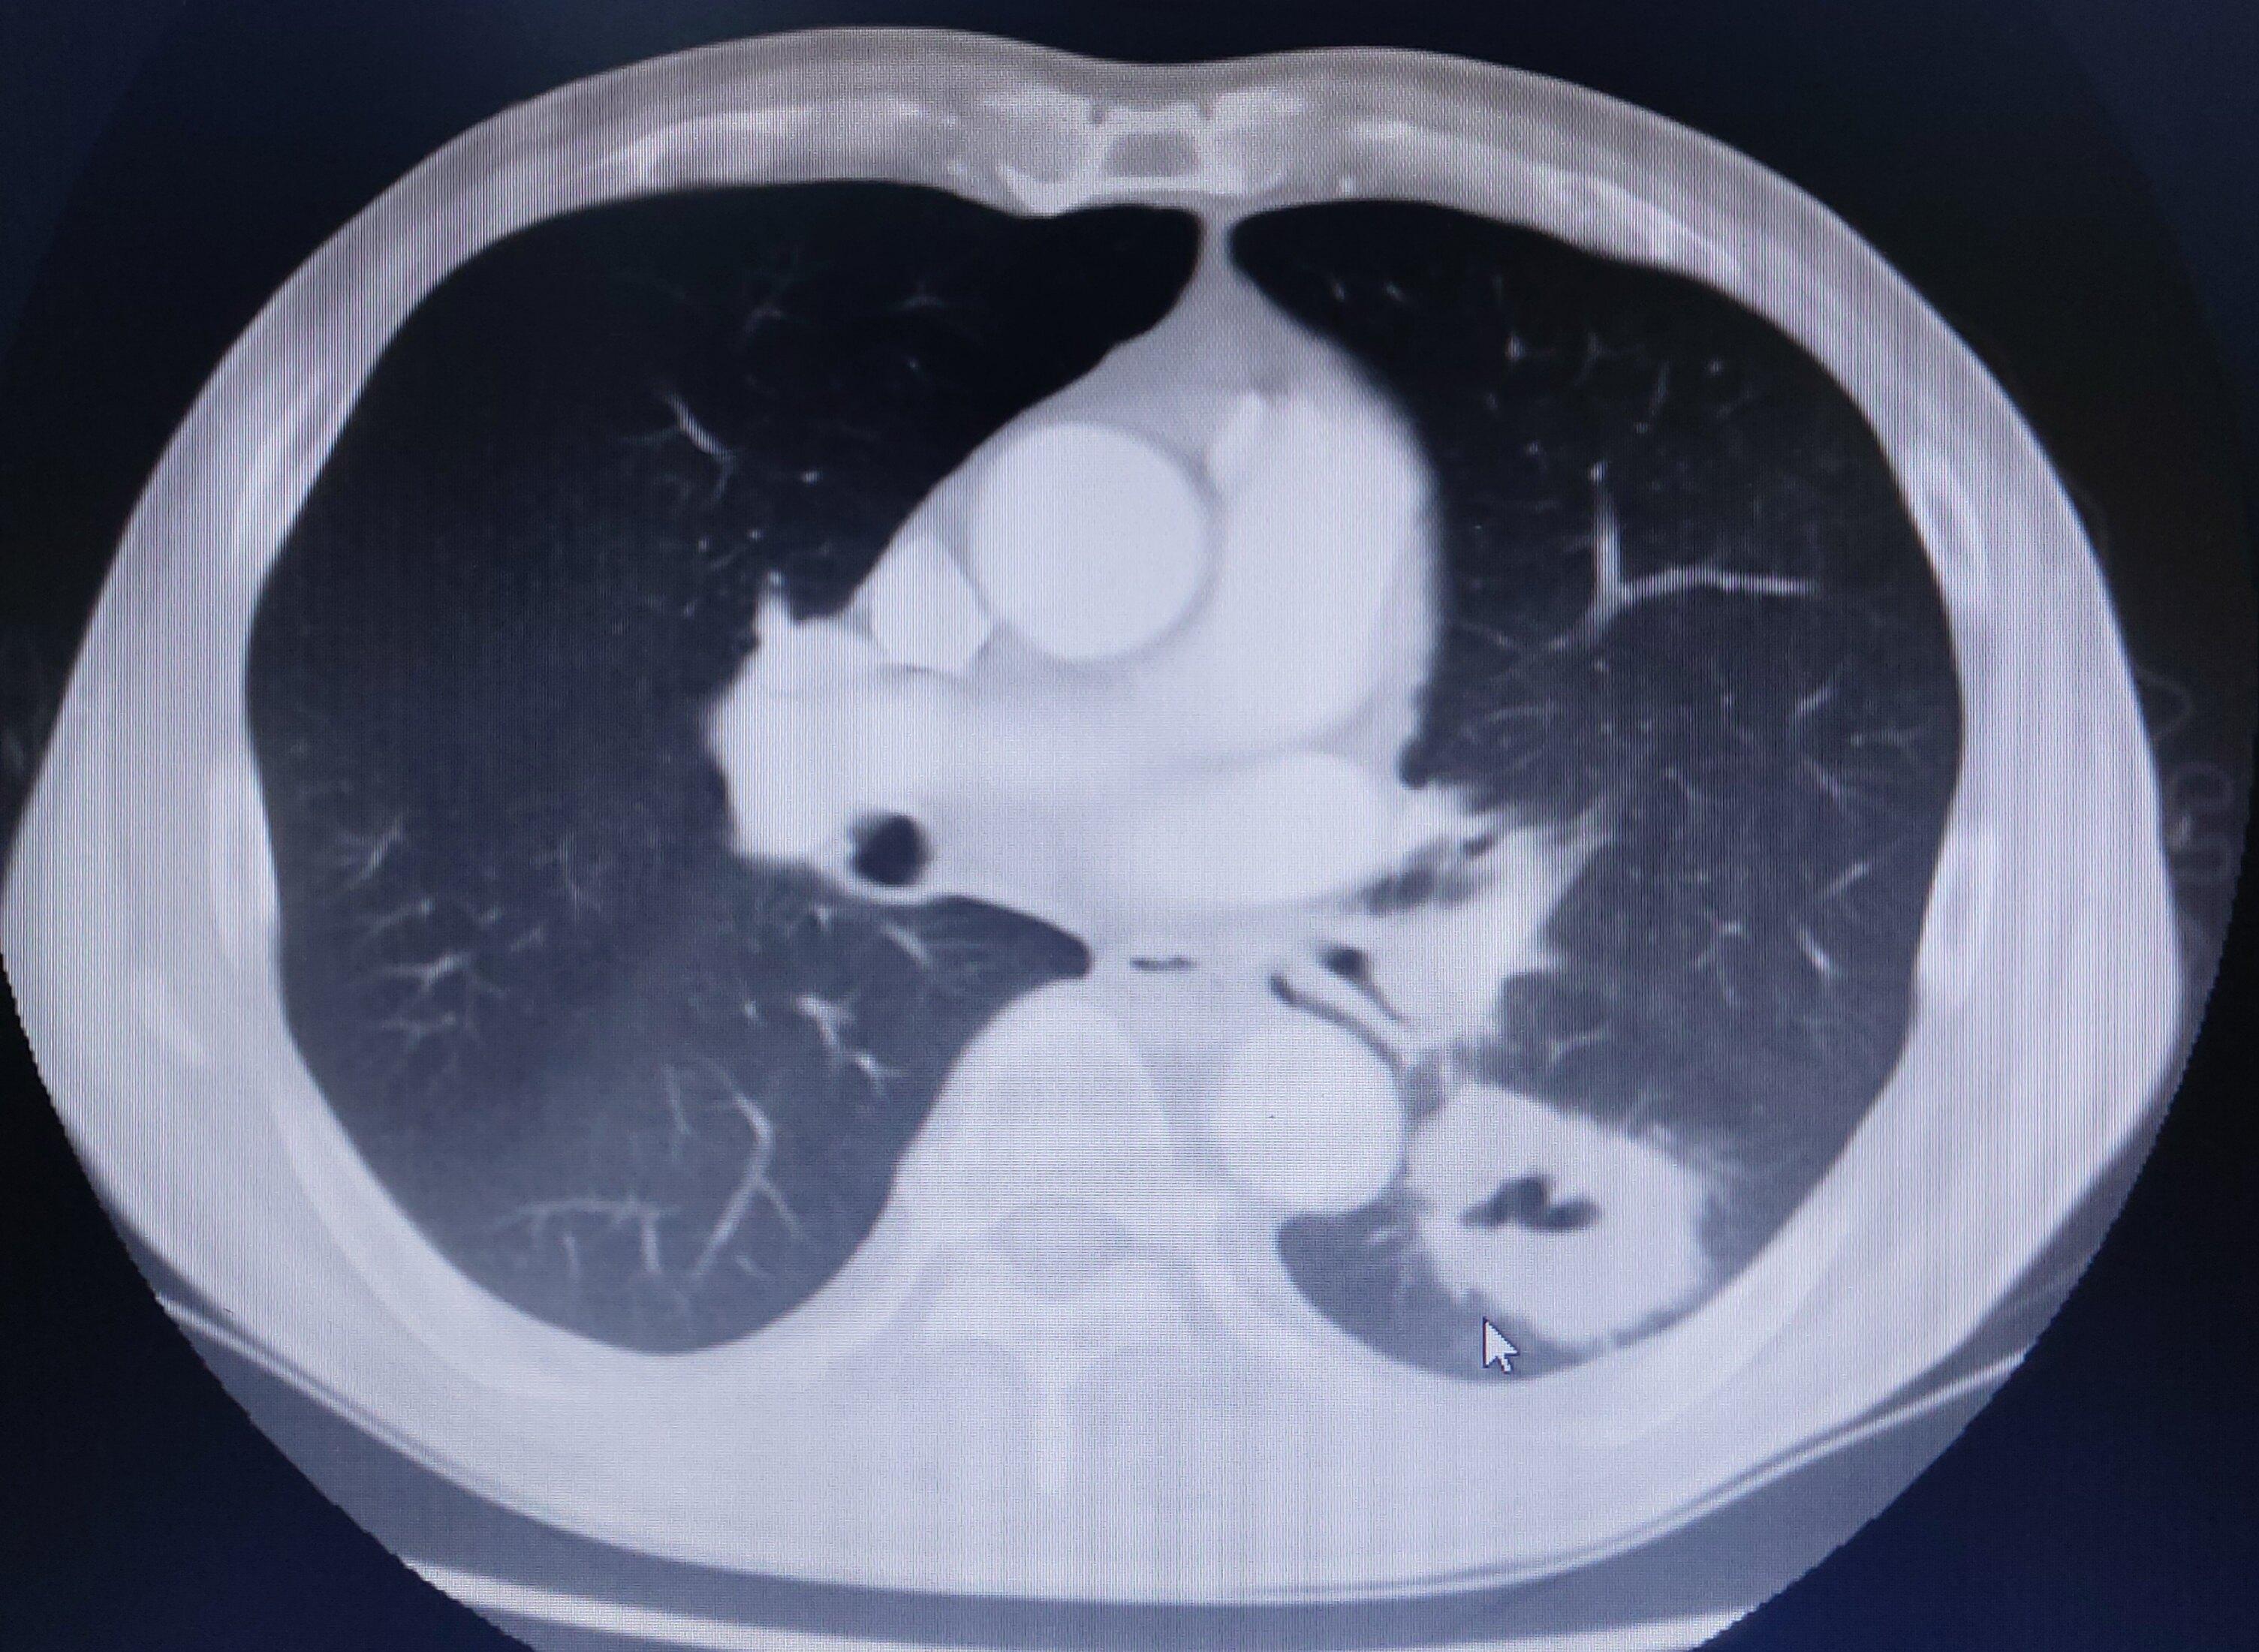

胸部ct平扫示左下肺占位——肺癌